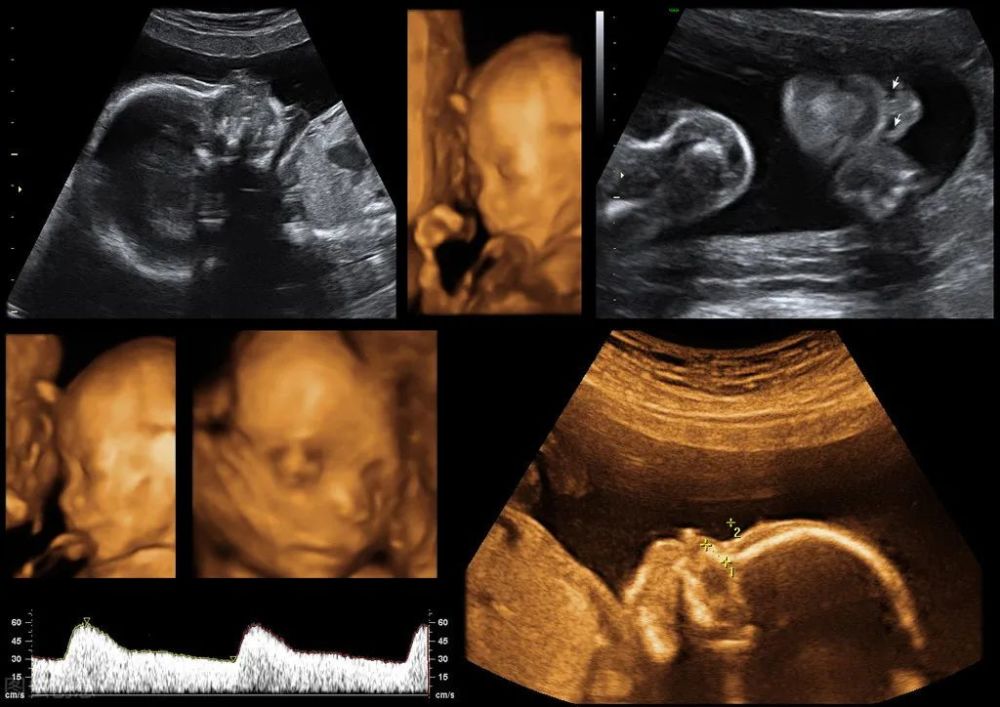

四维胎儿图片,四维图片胎儿全图

做四维彩超时,这些细节会透露胎儿性别?

胎儿四维照为何丑哭?"头大腿短"暗示什么?孕期四维必备知识点

胎儿的四维照片,跟实际相貌有区别吗?

四维图片胎儿全图

胎儿四维照片

四维彩超图片

胎儿四维

胎儿四维照片真实

四维彩超照片